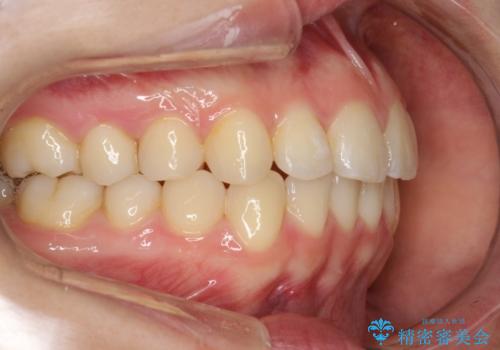

インビザラインによるガタつきの矯正治療 シンプル・短期間

- 20代女性

- invisalign full

- 1年6ヶ月

- 非抜歯、IPR+拡大によるマウスピース矯正を計画した。

一見前歯のガタつきだけのように見えても、そのガタつきの根本的な原因が奥歯の位置であったりすると、マウスピースの枚数がそれなりに多くなり、治療に時間がかかることもあります。